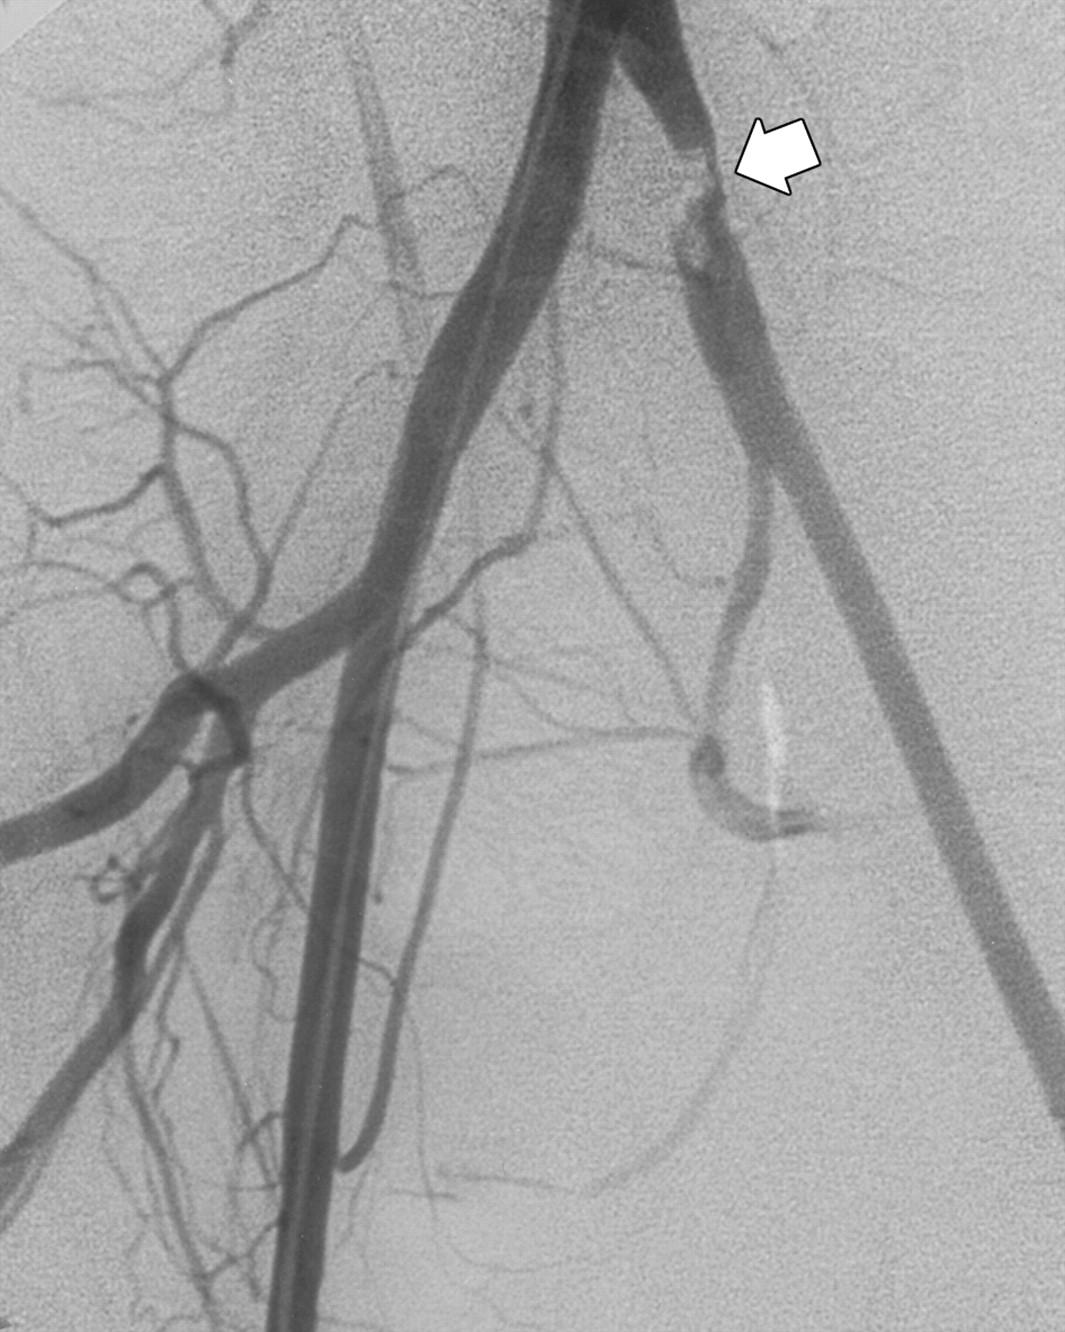

آنژیوگرافی عروق پا چیست و چه زمانی انجام می‌شود؟

• تعریف: آنژیوگرافی عروق پا یک روش تهاجمی تصویربرداری است که با تزریق ماده حاجب و گرفتن تصاویر از عروق پا، میزان شدت تنگی یا انسداد و محل دقیق آن را نشان می‌دهد.

• چه زمانی انجام می‌شود: در صورت وجود علائم PAD با احتمال بالای تنگی عروق، در مواقعی که تصویربرداری غیرتهاجمی مانند داپلر یا CT/MRI آنژیوگرافی اطلاعات کافی ارائه نکند، یا برای تصمیم‌گیری در مورد درمان داخل عروقی مانند استنت‌گذاری یا استنت‌گذاری، انجام می‌شود. همچنین پس از ارزیابی غیرتهاجمی برای تعیین نیاز به مداخله یا پایان دادن به تشخیص، انجام می‌گردد.

مراحل انجام آنژیوگرافی و استنت‌گذاری عروق پا

• حرکت کاتتر از طریق عروق به سمت ناحیه آسیب‌دیده و تزریق ماده حاجب برای نمایش بافت عروقی در تصاویر فلورسنس یا CT.

• تهیه تصاویر دقیق از طول عروق پا و شریان‌های پا.